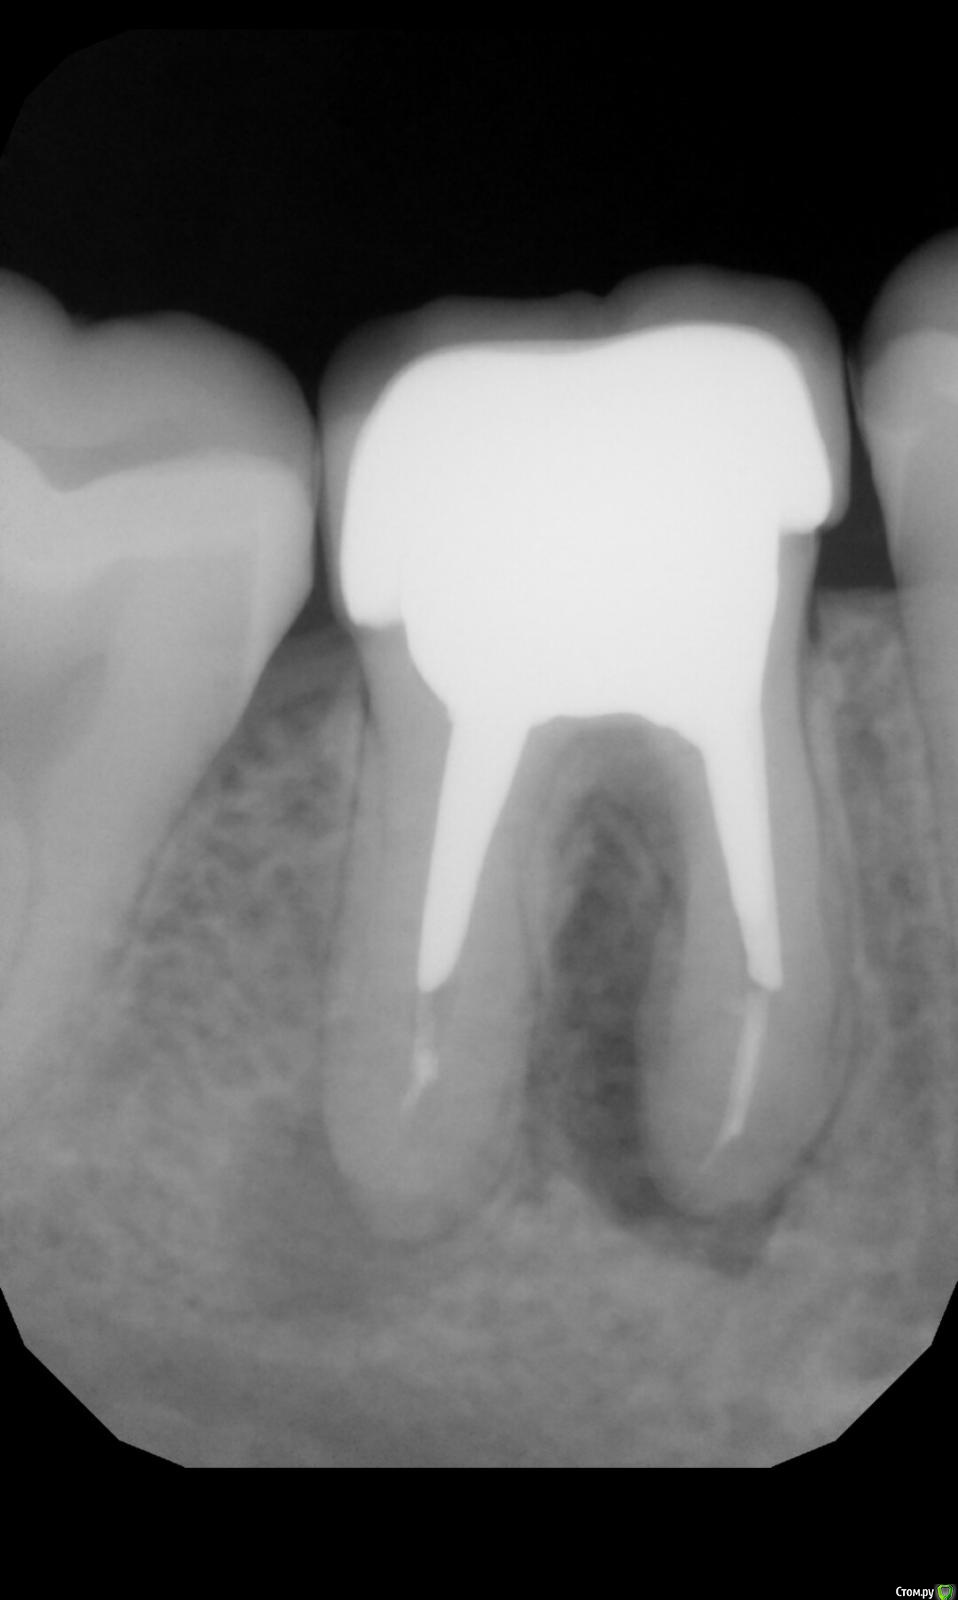

Mrs.guest Опубликовано 4 марта, 2019 Поделиться Опубликовано 4 марта, 2019 (изменено) Добрый вечер! 2.5 года назад депульпировали зуб и поставили коронку с вкладкой, зуб никак не тревожил и сейчас не болит. Вчера заметила уплотнение в десне около кости под этим зубом,шишку! при нажатии небольшая ,тупая боль,есть не мешает. Пошла к врачу,сделали снимок,врач сказала ,что зуб на удаление из-за того что воспаление уже сильное и вскрывать это все нет смысла,так как там все тонкое и зуб разрушится. Очень жалко зуб,так как к нему нет никаких претензий,коронка целая, жую хорошо, конечно же удалять жалко.. Я позвонила в клинику где мне это все устанавливали,они сказали прийти к ним завтра на приём и они посмотрят,если действительно по их вине пошло воспаление и нельзя исправить ,то удалят мне бесплатно зуб,но уверены ,что это не их вина. Подскажите чья это может быть вина, врача который лечил зуб или нет? Это как-то можно по снимку определить?И есть ли шанс и смысл сохранять зуб? Нудно независимое мнение,так как в этой клинике конечно же будут снимать вину с себя Изменено 4 марта, 2019 пользователем Mrs.guest Ссылка на комментарий

Mrs.guest Опубликовано 4 марта, 2019 Автор Поделиться Опубликовано 4 марта, 2019 (изменено) Снимок приложила Изменено 4 марта, 2019 пользователем Mrs.guest Ссылка на комментарий

kramer Опубликовано 11 марта, 2019 Поделиться Опубликовано 11 марта, 2019 Здравствуйте. Вы зачем-то ищите виноватых, это вас никуда не приведет. На исход лечения каналов гарантий не существует, к тому же мы не знаем, что было до эндодонтического лечения. Так или иначе вокруг корней есть воспаление, которое можно попытаться устранить перелечиванием каналов (опять же без гарантии). Сложность в том, что коронка установлена на культевую вкладку, извлечение которой из каналов может привести к утрате собственных тканей зуба и его ослаблению и как следствие невозможности его сохранения... Каким путем идти решать вам 1 Ссылка на комментарий

Pavel-Pskov Опубликовано 11 марта, 2019 Поделиться Опубликовано 11 марта, 2019 Кмк там ещё между корнями процесс, а это вряд ли лечится. Ссылка на комментарий